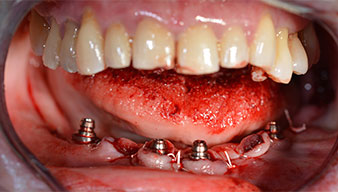

Angled abutments (35°) were screwed in to compensate for the divergence of the distal implants, with the result that the emergence profile of all implants was as perpendicular as possible to the bite plane. This is a prerequisite for occlusal placement of the provisional and subsequently the permanent denture (Fig. 15 and 16).

Implants

Fig. 15

Fig. 16

The impression and bite registration were then performed so that the dental technician could begin producing the provisional restoration immediately. This was then screwed in on the same day (Fig. 17 and 18).

Fig. 17

Fig. 18